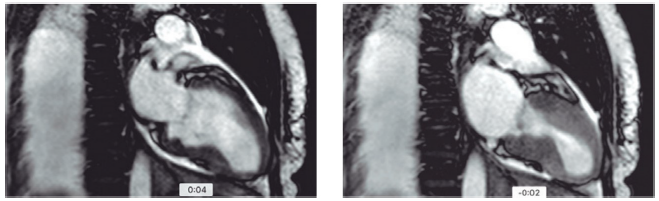

Mulher de 74 anos, obesa, com histórico de depressão, doença renal crônica em estágio III A, chegou ao pronto socorro relatando quadro de dor precordial em opressão e dispneia de início há 30 minutos, após intensa discussão com familiares sobre política. Ao exame físico, apresentou: PA =140x74 mmHg; FC = 100 bpm; ritmo cardíaco regular em dois tempos; bulhas normofonéticas sem sopro; murmúrio vesicular presente sem ruídos adventícios, pulsos presentes e simétricos, sem edema. Foi realizada a cinecoronariografia, devido aos sintomas prolongados e às alterações eletrocardiográficas, que mostrou lesão de 30% em DA e irregularidades em CD; não foi realizada a ventriculografia, a troponina elevou-se acima do percentil 99 e fez curva. Devido à janela ecocardiográfica ruim, foi solicitada a ressonância cardíaca abaixo, que mostrou a diástole (à esquerda) e a sístole (à direita). Ausência de alterações no realce tardio.